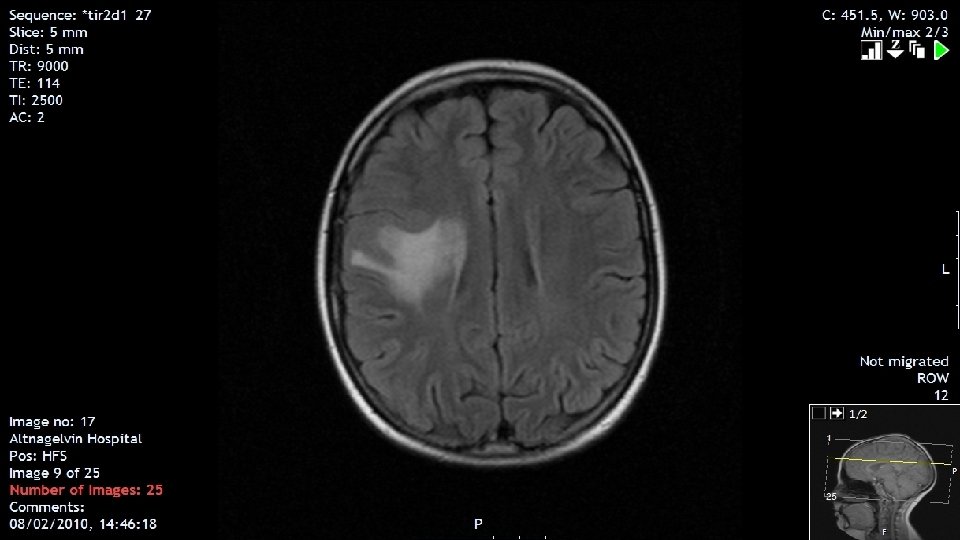

Late Effect Second Malignancy 2010 aged 20 years • Seizures post thyroidectomy. CT and MRI revealed a meningioma • RVH Subtotal removal of right sided meningioma grade 2. No radiotherapy due to previous treatment for AML. On Lamictal for seizure control 2013 aged 23 years • Progression of Meningioma further increase in size of residual tumour 2014 aged 24 years • Stereotactic radiosurgery in Leeds ( gamma knife)